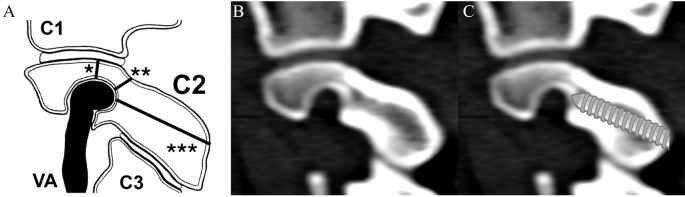

Somatom Sensation 64 (Siemens Healthineers, Erlangen, Germany) was used to acquire CT scans. The standard imaging protocol included a tube voltage of 120 kVp with automatic tube current modulation. Axial images were reconstructed using a slice thickness of 0.6 mm, applying a high-resolution bone kernel (B60f.). The matrix size was 512 × 512, and the field of view was adapted individually to cover the cervical spine. Scans were performed with the patient in the supine position, head-first, with the scan range extending from the base of the skull to the upper thoracic spine. HRVA was defined as uniformly accepted: C2 isthmus height (C2IsH) of ≤ 5 mm and/or C2 internal height (C2InH) of ≤ 2 mm measured 3 mm lateral to the lateral border of the spinal canal1,2,7. Measurements of pars length were taken using the method described by Kothari et al.8—see Fig. 1. We used Horos—an open-source code software distributed under the LGPL license at Horosproject.org and sponsored by Nimble Co LLC d/b/a Purview (Annapolis, MD, USA). The measurements took place from October till December 2024. As calculated by us in our previous study7, the interobserver, intraobserver, and intersoftware coefficients for HRVA measurements are all either good or excellent, therefore a second observer was not invited to replicate the results this time.

(A) The schematic presentation of C2 parameters measured in the study: *internal height, **isthmus height, ***pars interarticularis length. VA—vertebral artery. (B) The unaltered sagittal computed tomography (CT) slice showing the raw “in situ” anatomy. (C) the sagittal CT slice with the simulated pars screw trajectory, roughly paralleling C2/C3 zygapophyseal joint. Created with assistance of Biorender.com.